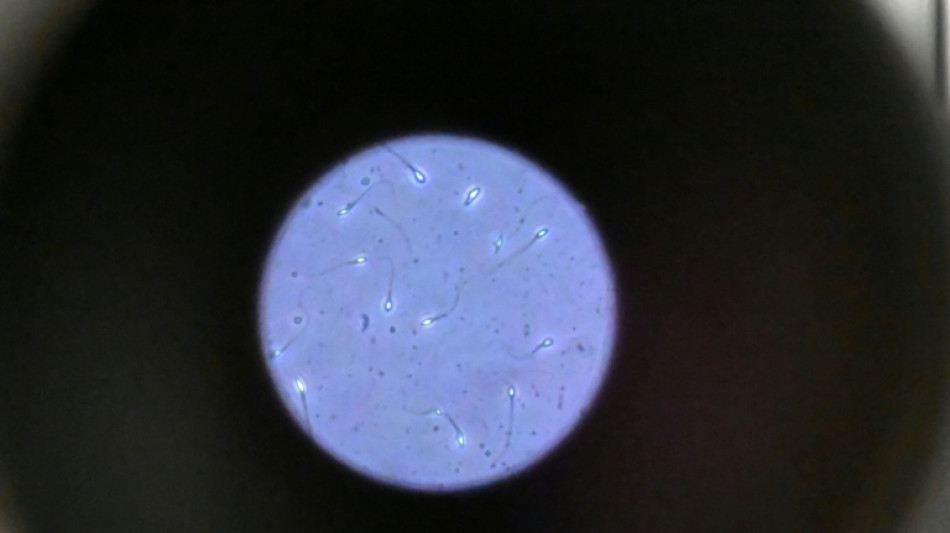

Dans l'espace, les spermatozoïdes ont du mal à trouver leur chemin / Photo: © AFP/Archives

Dans l'espace, les spermatozoïdes ont du mal à trouver leur chemin vers l'ovule en raison de la microgravité, qui perturbe aussi le développement des embryons, selon une étude publiée jeudi dans Communications Biology.

Les chercheurs ont testé successivement du sperme de souris et humain dans ce dispositif placé dans un appareil en constante rotation pour simuler la microgravité.

Les gamètes ont été environ 50 % moins performants pour naviguer à travers ce parcours que sous la gravité terrestre. Cela équivaut à une baisse de 30% du taux de fécondation réussie, selon les résultats de l'étude.

Les spermatozoïdes ayant réussi à franchir le parcours semblaient produire des embryons de meilleure qualité.

Il semble que le stress lié à la microgravité ait agi comme un "filtre" éliminant les plus faibles et "ne laissant en lice que les plus performants", ce qui pourrait s'avérer "bénéfique", selon Mme McPherson.